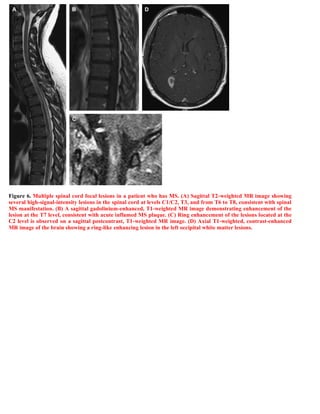

This document discusses a case of spinal multiple sclerosis in a 40-year-old patient. MRI images show well-defined pencil-shaped lesions occupying 2-3 spinal segments that are hypointense on T1-weighted images and hyperintense on T2-weighted images. Diffuse abnormalities are also seen as poorly demarcated hyperintense regions on T2-weighted images. The diagnosis is spinal multiple sclerosis. The document then discusses features of spinal MS lesions seen on MRI such as focal lesions, diffuse abnormalities, and spinal cord atrophy, and compares features of MS to other conditions like neuromyelitis optica.